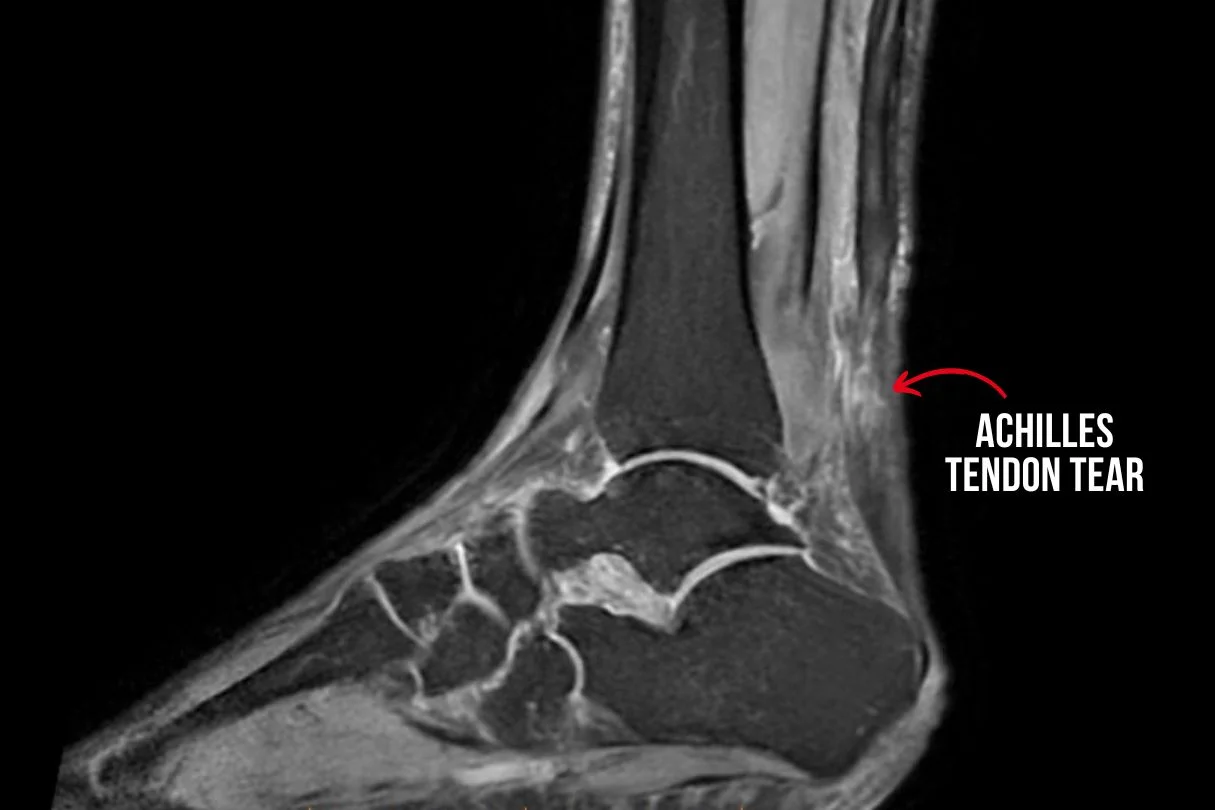

MRI image showing complete Achilles Tendon tear

Diagnostic tests such as ultrasound or MRI scans are typically necessary to confirm the extent of the injury. Treatment options will depend on the severity of the tear but commonly include: